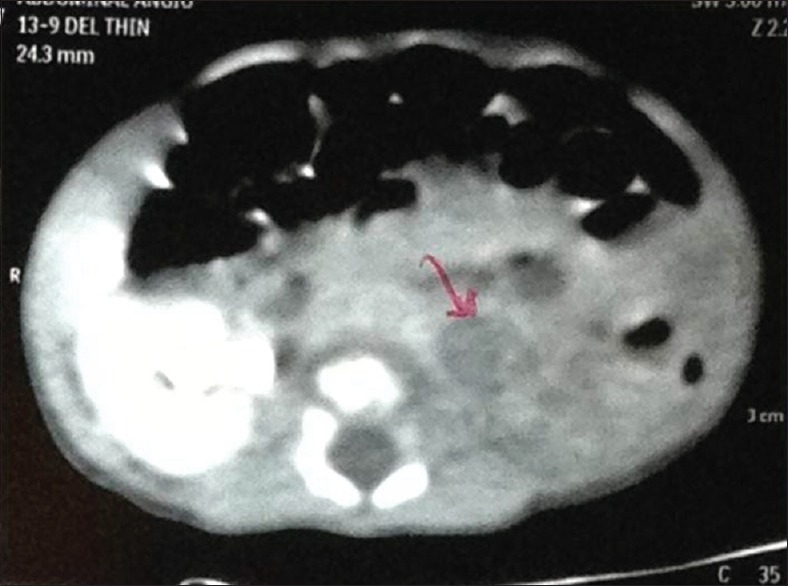

Urine vanillylmandelic acid levels were normal; plasma metanephrine levels were mildly raised. Fundoscopy was normal. Computed tomography (CT) showed left kidney 4.3 cm × 2.6 cm in size with no nephrogram and no contrast excretion seen. An ill-defined isodense lesion 1.1 cm × 0.9 cm seen in left renal hilum with few calcific specks [Figures [Figures11 and and22].

| Figure 2:Computed tomography showed no nephrogram and no contrast excretion on the left side